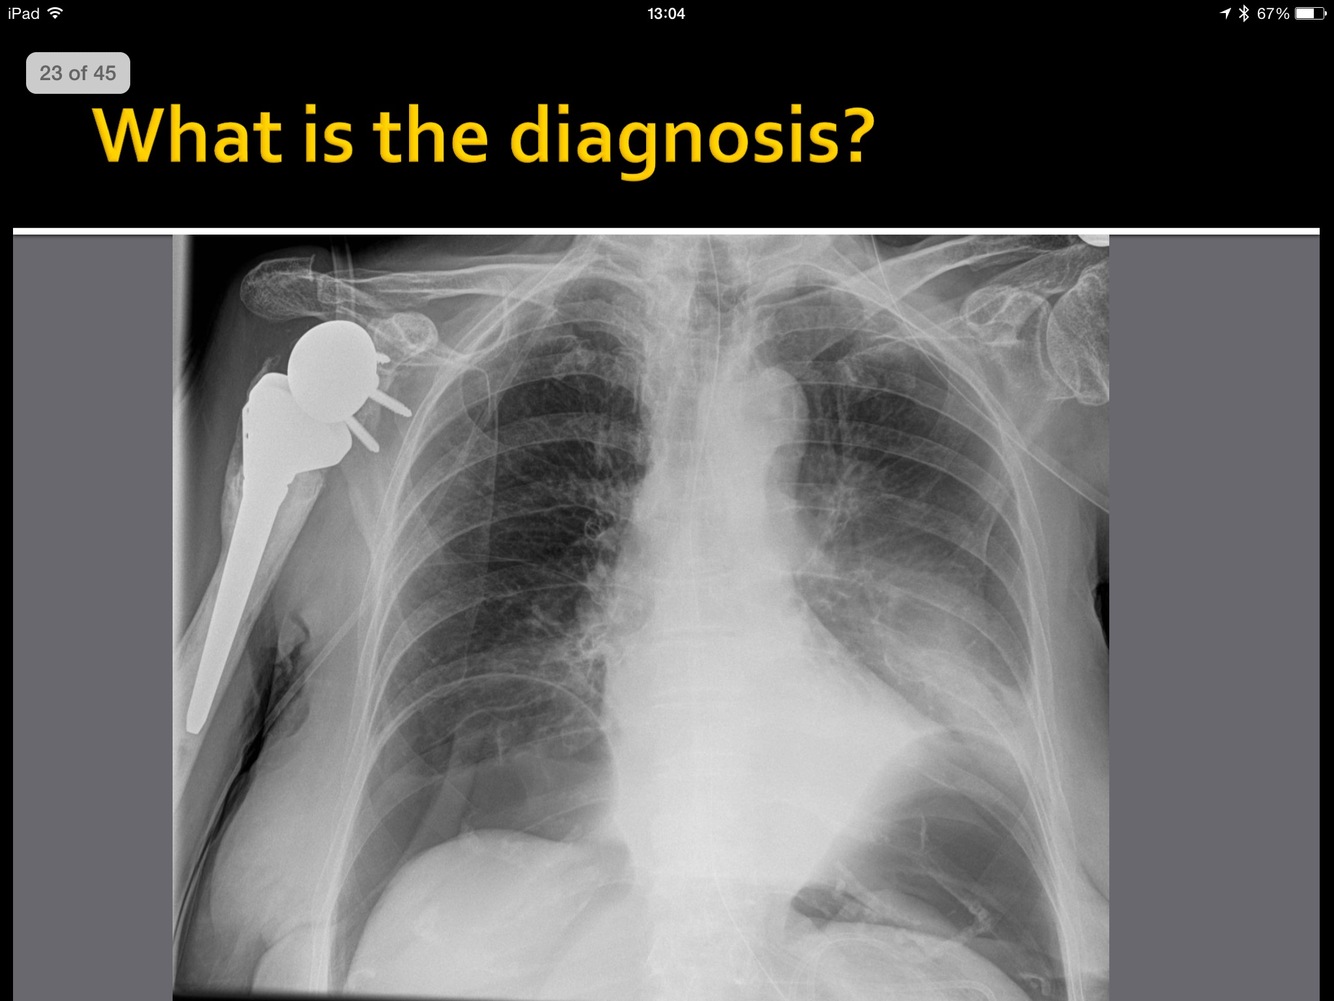

What is the pathology here?